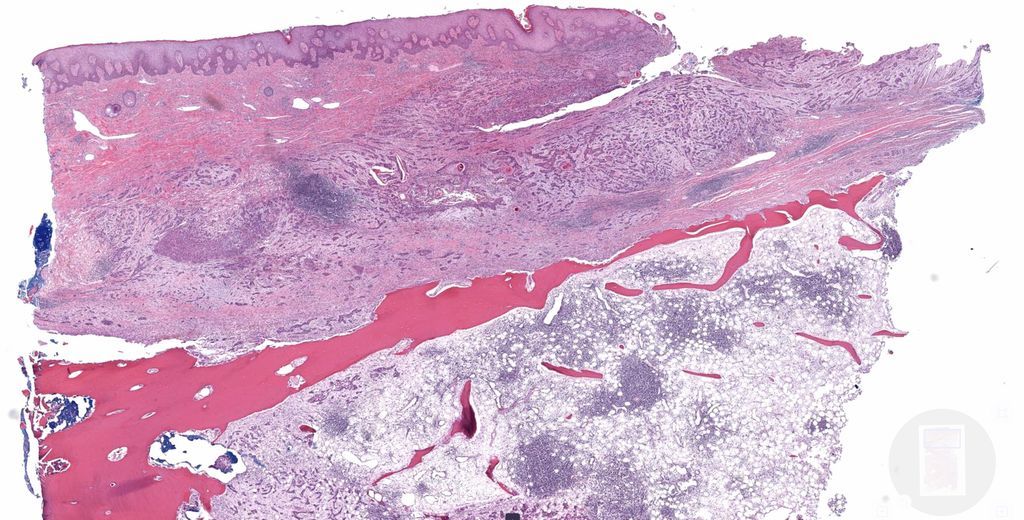

20 yo woman. Bilateral groin excisions. Answer ✅ https://t.co/Xhk08Y4pSt WSI digital slides: https://t.co/I2BQy4Sb33

#pathology #pathologists #pathTwitter #dermpath #dermatology #dermatologia #dermtwitter